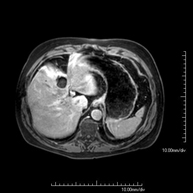

- RM Abdomen

Prueba diagnóstica no invasiva que consiste en la obtención de imágenes de alta definición anatómica del abdomen mediante el empleo de un campo electromagnético y ondas de radio (con un emisor y un receptor). No utiliza radiación ionizante. En esta exploración se incluyen el hígado, páncreas, bazo, vía biliar, vesícula biliar,Entero-RM glándulas suprarrenales, riñones, aorta abdominal, vena cava inferior, estómago, duodeno,…En ocasiones se deberá emplear contraste paramagnético (Gadolinio) para caracterizar las lesiones. - RM Pelvis femenina

- RM Hígado

Prueba diagnóstica no invasiva que consiste en la obtención de imágenes de alta definición anatómica del hígado mediante el empleo de un campo electromagnético y ondas de radio (con un emisor y un receptor). No utiliza radiación ionizante. Se realiza para estudiar cualquier lesión localizada en el hígado, y también para valorar enfermedades inflamatorias y de depósito. Normalmente se requiere el uso de contraste paramagnético (Gadolinio) para caracterizar las lesiones. Es necesario realizar la prueba en ayunas (6 horas). - RM Riñones